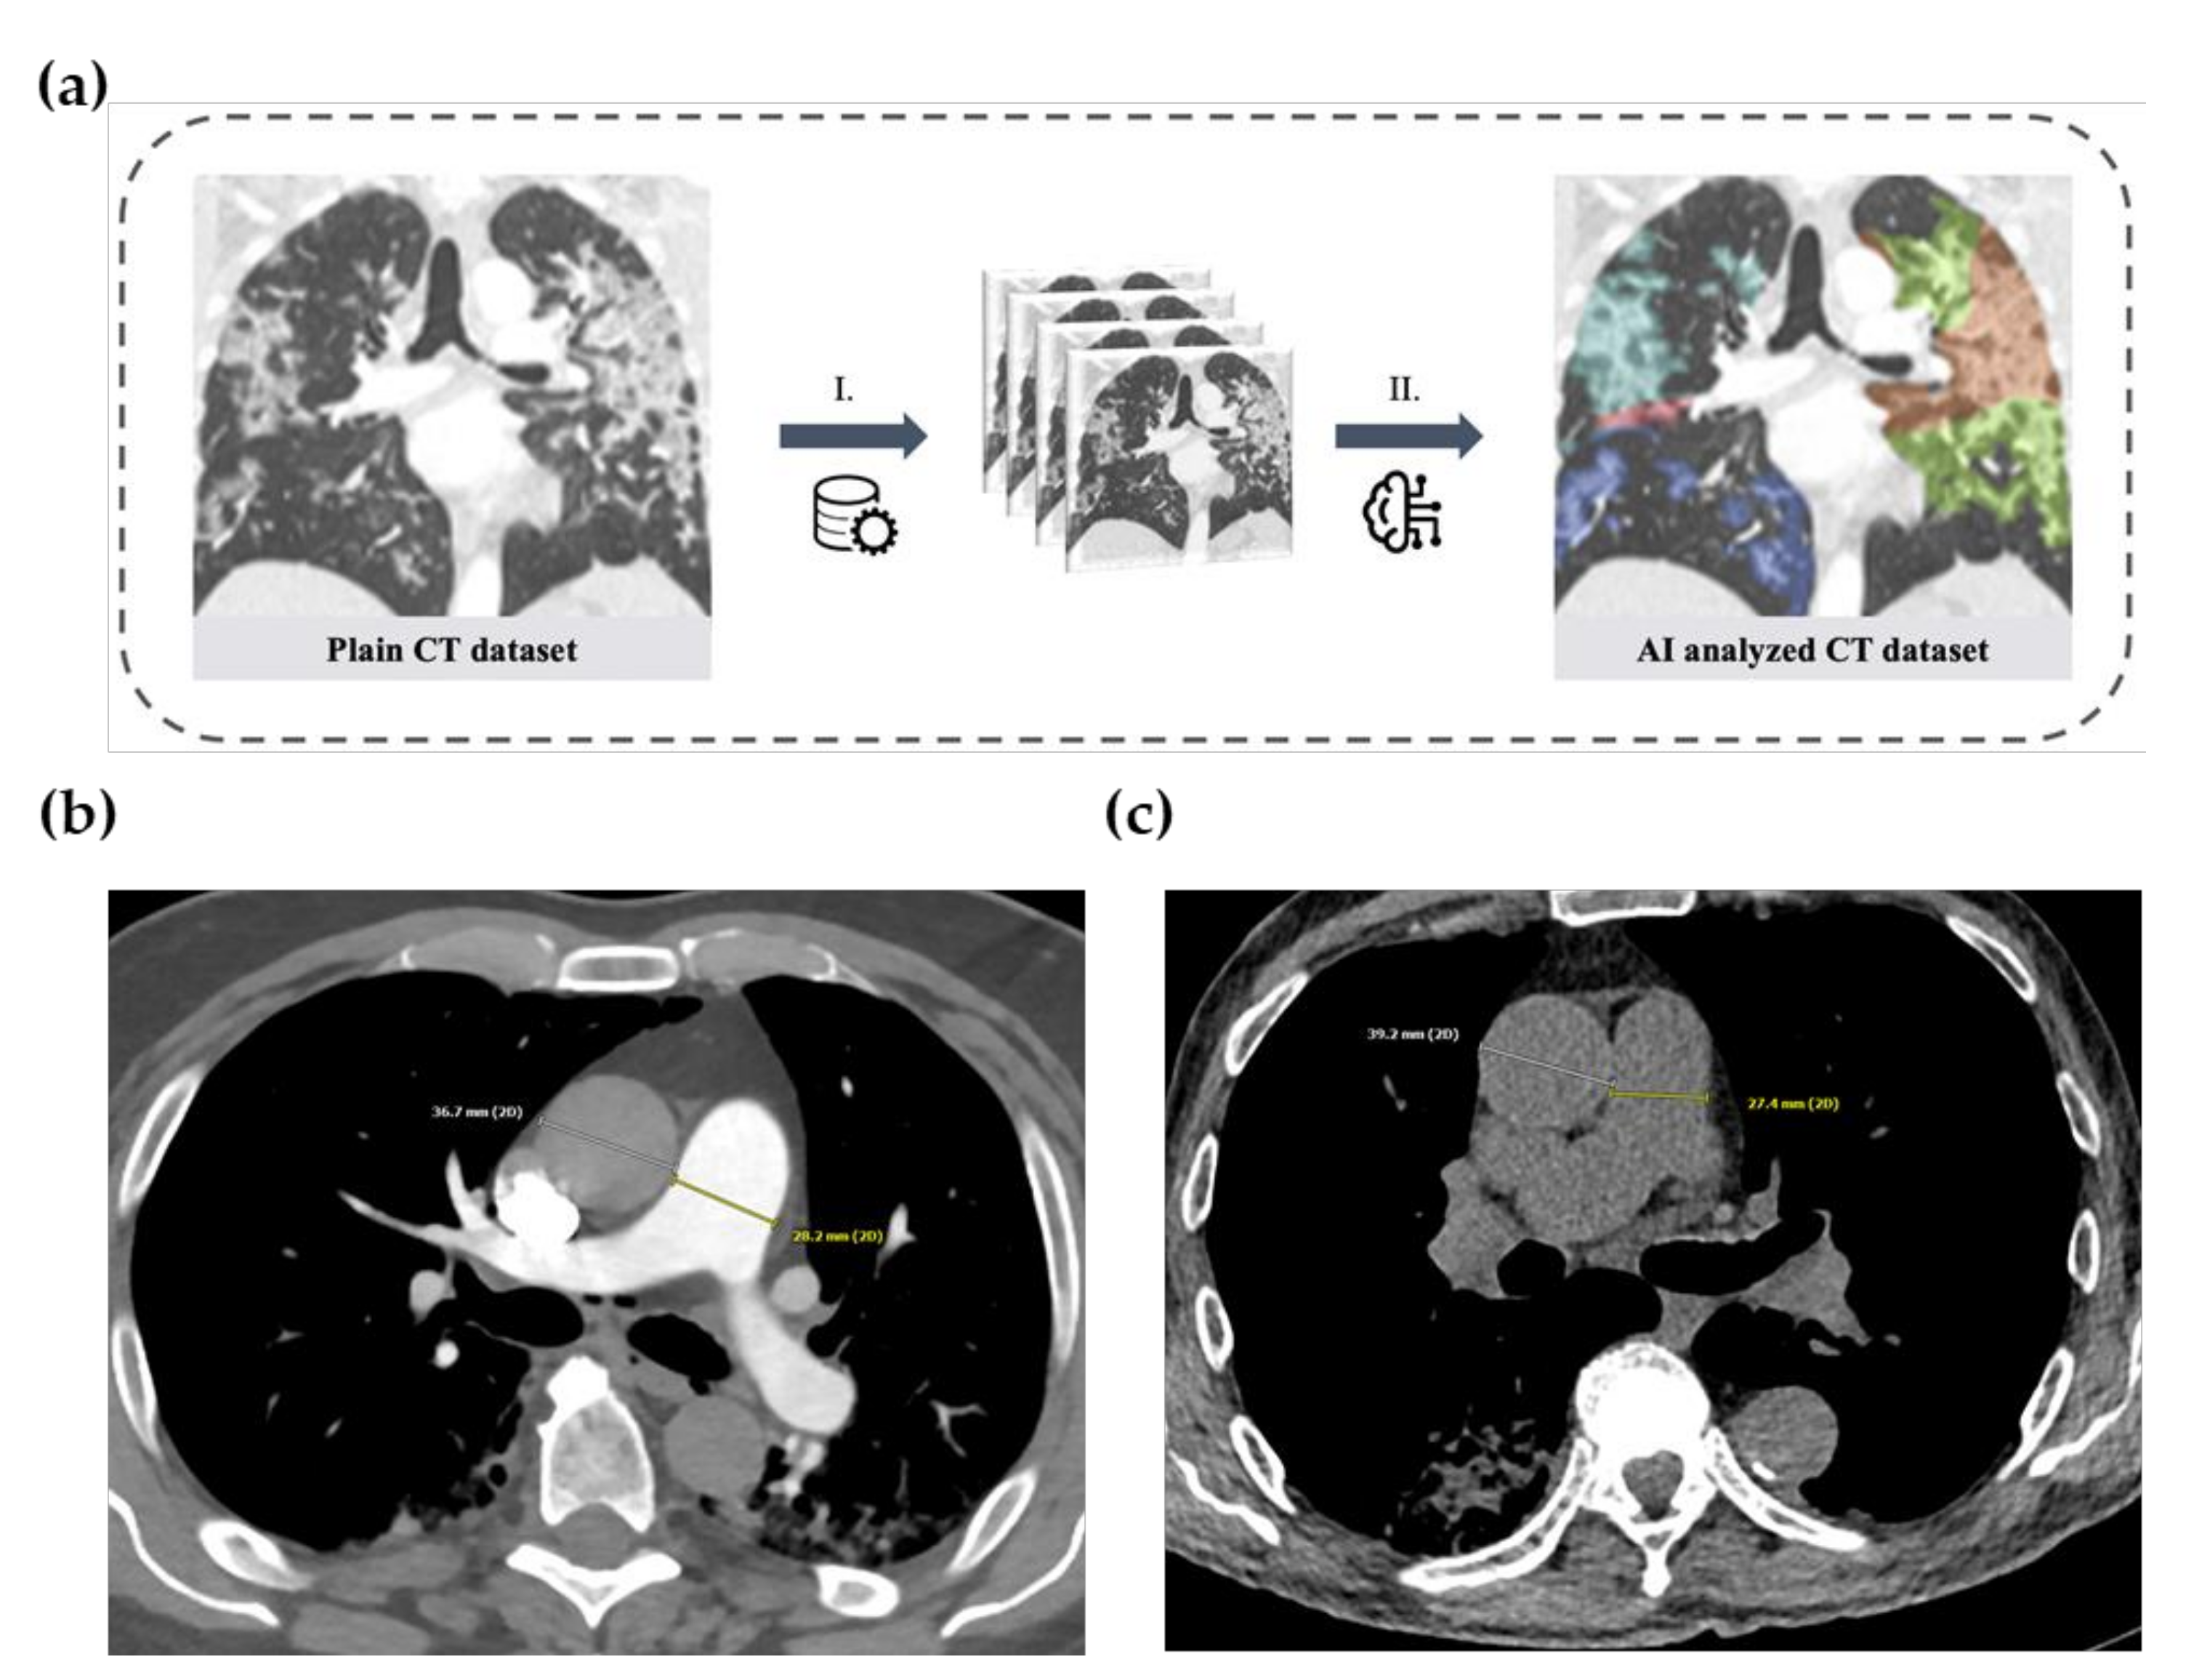

2.3. Artificial-Intelligence-Based Quantification of Lung Involvement